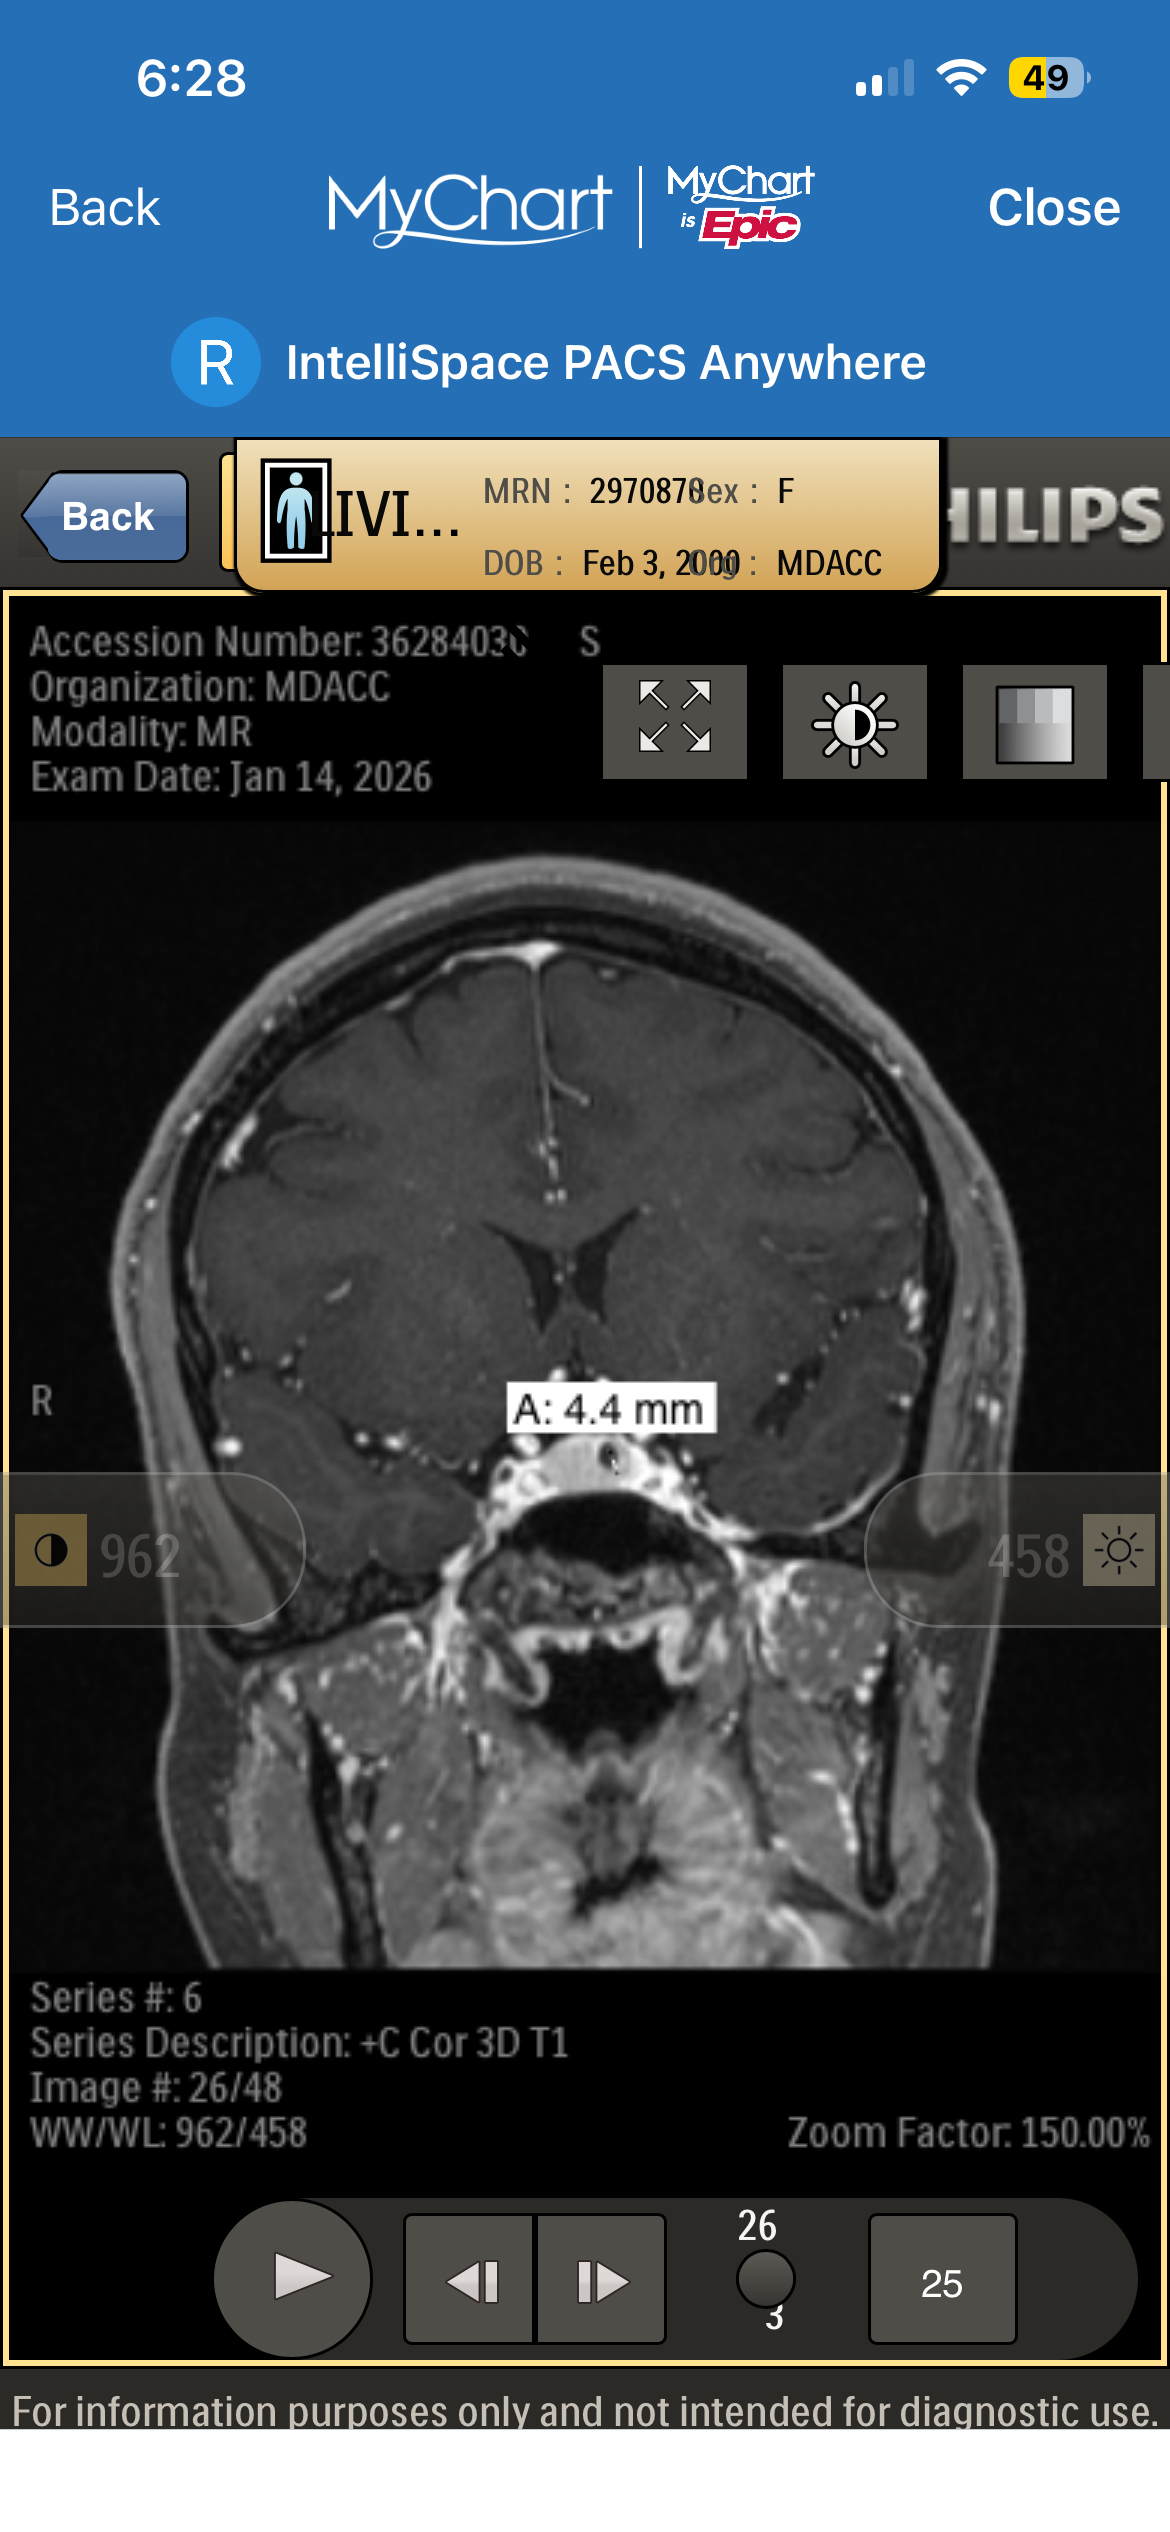

Recently, I was diagnosed with a pituitary brain tumor. Since then, my life—and my family’s—has changed in ways we couldn’t have prepared for. Between medical appointments, testing, treatment planning, and travel for specialized care, the financial and emotional weight has become heavy very quickly.